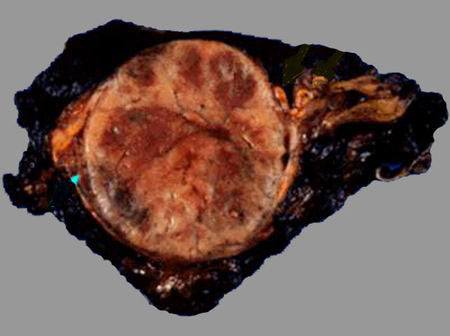

Феохромоцитома представляет инкапсулированную опухоль с хорошей васкуляризацией, размером около 5 см и средней массой до 70 г. Встречаются феохромоцитомы как больших, так и меньших размеров; при этом степень гормональной активности не зависит от величины опухоли.